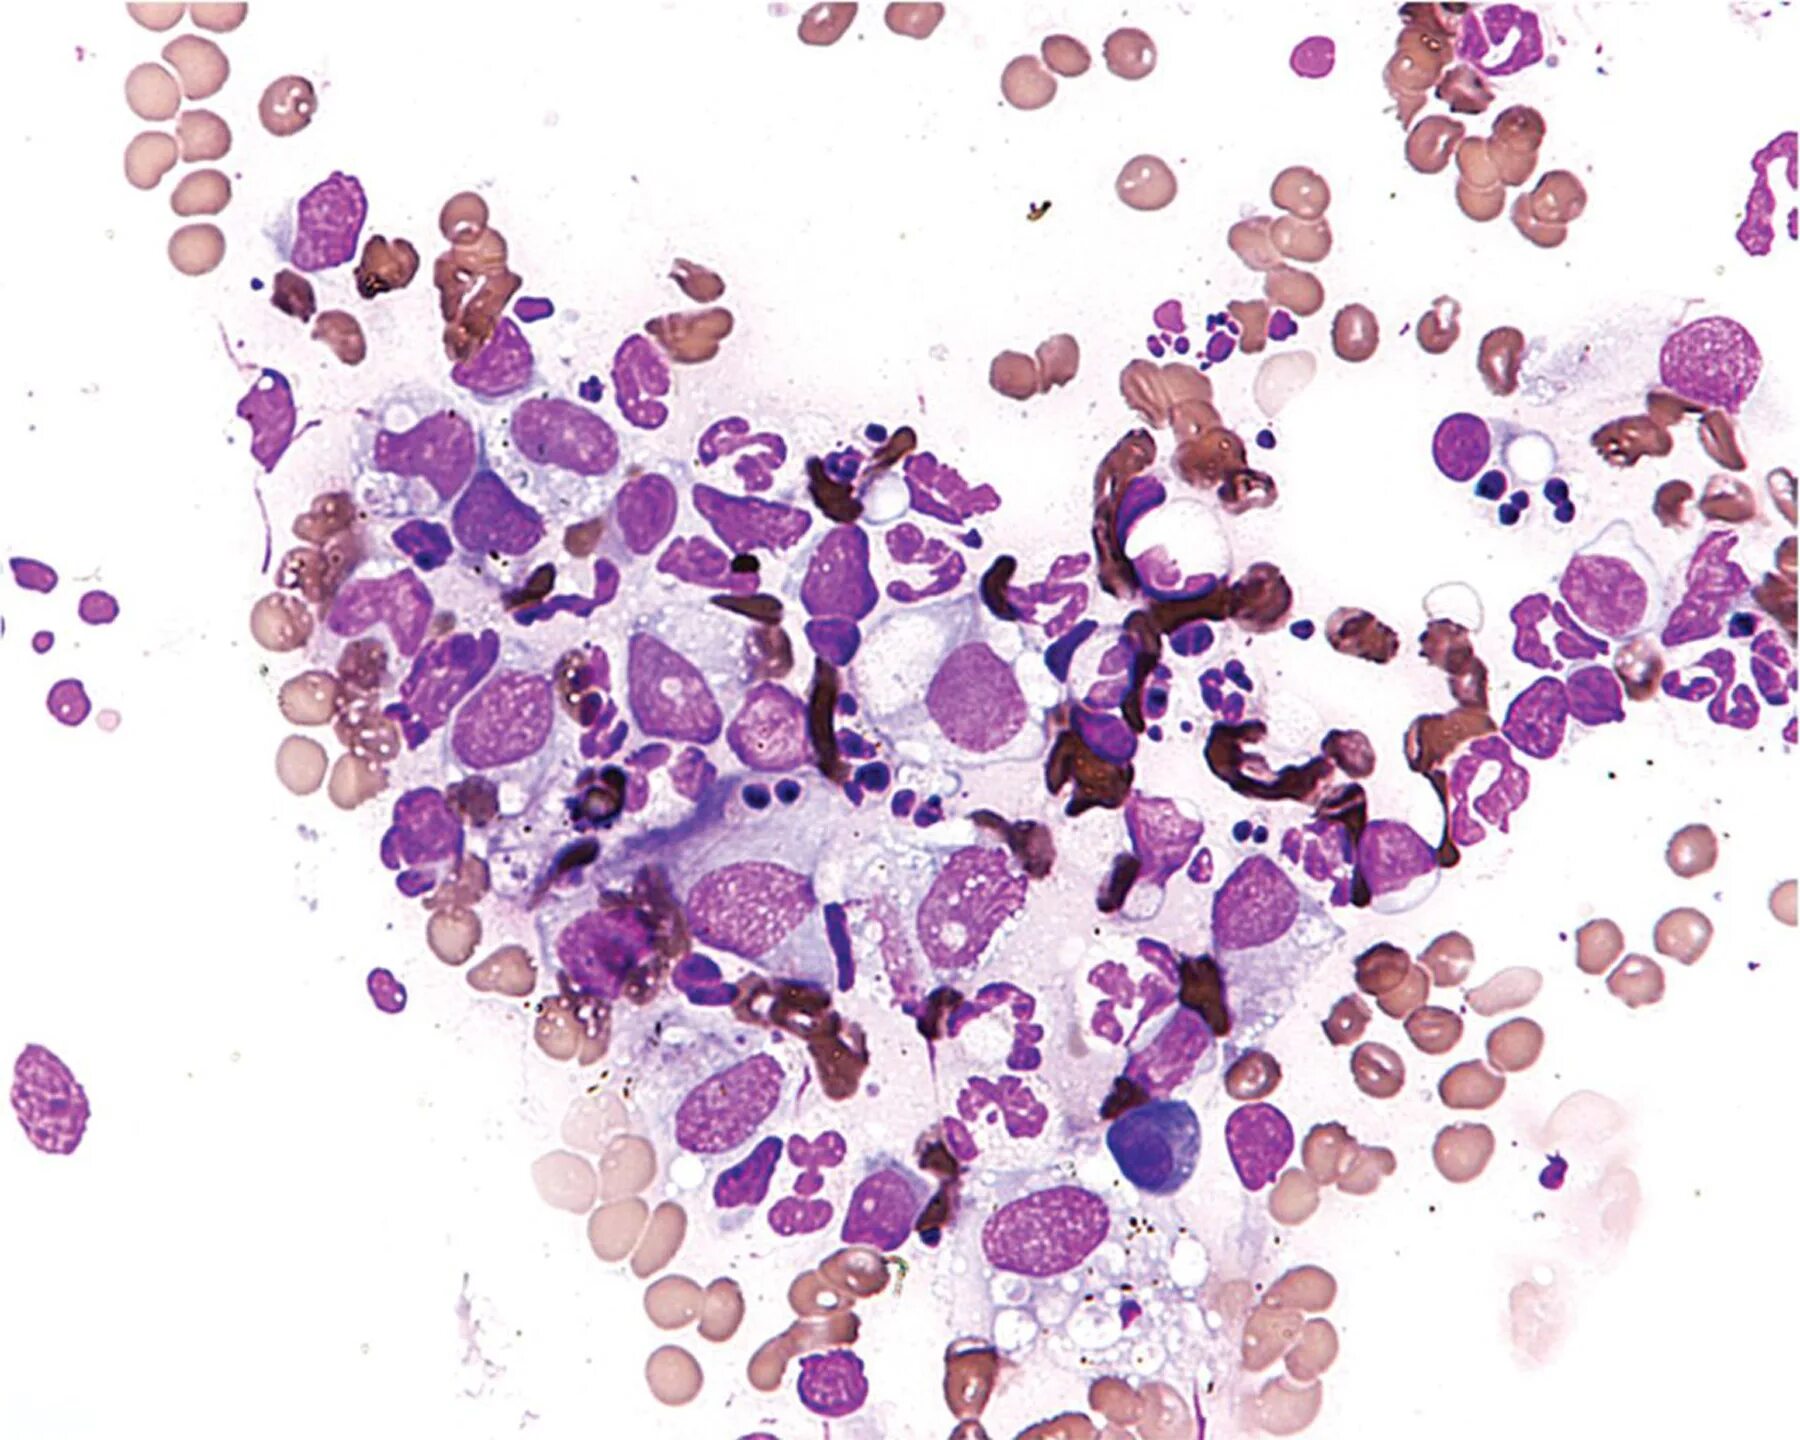

Анализ мазка микрофлора кокки. кокко-бациллярная микрофлора в мазке у женщин.Микрофлора коккобациллярная что это у женщинМикрофлора коккобациллярная что это у женщинГрамположительные палочки в анализе. микрофлора мазка у женщин. грамм положительные палочки в мазке норма?.Микрофлора коккобациллярная что это у женщинАнализ мазка микрофлора кокки. норма кокков в мазке. грамотрицательные кокки в мазке у женщин.Микрофлора коккобациллярная что это у женщинМикрофлора коккобациллярная что это у женщинМикрофлора коккобациллярная что это у женщинМикрофлора коккобациллярная что это у женщинАнализ мазка микрофлора кокки. анализ микрофлоры коккобациллярная. микрофлора палочки кокки мазок норма.Микроскопическое исследование отделяемого уретры. исследование мазков отделяемого мочеполовых органов. коккобациллярная микрофлора.Лептотрикс в мазке на флору. мазок на степень чистоты. коккобациллы у женщины в мазке на флору.Бациллярная умеренная. бациллярная микрофлора.Микрофлора коккобациллярная что это у женщинМикрофлора коккобациллярная что это у женщинМикрофлора коккобациллярная что это у женщинНорма грамм(+) кокки в мазке на флору. норма кокков в мазке. грамотрицательные кокки в мазке у женщин.Микрофлора коккобациллярная что это у женщинМазок на флору бациллярная. бациллярная микрофлора в мазке.Исследование гинекологического мазка норма. анализ мазка микрофлора кокки.Микрофлора мазка у женщин.Норма грамм(+) кокки в мазке на флору. микрофлора смешанная скудная.Мазок на флору норма палочки. анализ мазка микрофлора кокки. микрофлора палочки в мазке у мужчин.Микрофлора коккобациллярная что это у женщинСмешанная микрофлора. грамвариабельные бациллы. грамвариабельные это.Микрофлора коккобациллярная что это у женщинМикрофлора коккобациллярная что это у женщинМикрофлора коккобациллярная что это у женщинМикрофлора коккобациллярная что это у женщинМикрофлора коккобациллярная что это у женщинМикрофлора коккобациллярная что это у женщинМикрофлора коккобациллярная что это у женщинМикрофлора коккобациллярная что это у женщинМикрофлора коккобациллярная что это у женщинМикрофлора коккобациллярная что это у женщинМикрофлора коккобациллярная что это у женщинМикрофлора коккобациллярная что это у женщинПсевдомицелий кандида. грибы candida псевдомицелий. коккобациллярная форма.Микрофлора коккобациллярная что это у женщинМикрофлора коккобациллярная что это у женщинМикрофлора коккобациллярная что это у женщинЛептотрикс кокки. коккобациллы микроскопия. грамвариабельная коккобациллярная.Микрофлора коккобациллярная что это у женщинМикрофлора коккобациллярная что это у женщинМикрофлора коккобациллярная что это у женщинМикрофлора коккобациллярная что это у женщинКоккобациллярная микрофлора. коккобациллярная микрофлора в мазке у женщин.Микрофлора палочки кокки мазок норма. анализ мазка микрофлора кокки. исследование мазков отделяемого мочеполовых органов.Микрофлора коккобациллярная что это у женщинМикрофлора коккобациллярная что это у женщинМикрофлора коккобациллярная что это у женщинМикрофлора коккобациллярная что это у женщинМикроскопическое исследование мазка у женщин. анализ на микрофлору. палочки умеренно в мазке.Микрофлора коккобациллярная что это у женщинМикрофлора коккобациллярная что это у женщинМикрофлора коккобациллярная что это у женщинНорма кокков в мазке. кокковая микрофлора в мазке.Микрофлора коккобациллярная что это у женщинМикрофлора коккобациллярная что это у женщинМазок на флору у женщин норма палочки.Кокковая микрофлора в мазке. норма грамм(+) кокки в мазке на флору.Микрофлора коккобациллярная что это у женщинАнализ мазка микрофлора кокки. норма кокков в мазке.Микрофлора коккобациллярная что это у женщинГрам палочки в мазке. микрофлора грамм + палочки в большом количестве. грам кокки в мазке у женщин.Микрофлора коккобациллярная что это у женщинМикрофлора коккобациллярная что это у женщинМикрофлора коккобациллярная что это у женщинМикрофлора коккобациллярная что это у женщинМикрофлора коккобациллярная что это у женщинЭпителий из уретры у женщин норма таблица. лейкоциты в поле зрения в мазке у женщин норма. анализ на эпителий кошки расшифровка. эпителий умеренное количество в мазке у женщин что это.